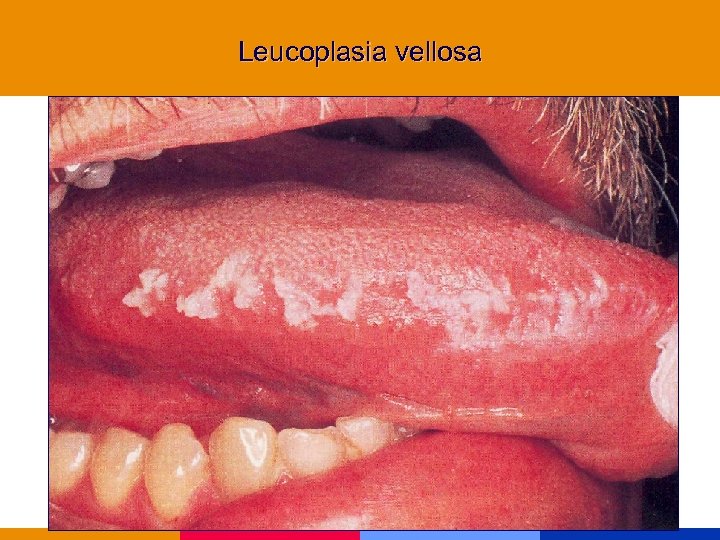

Leucoplasia vellosa

Leucoplasia vellosa